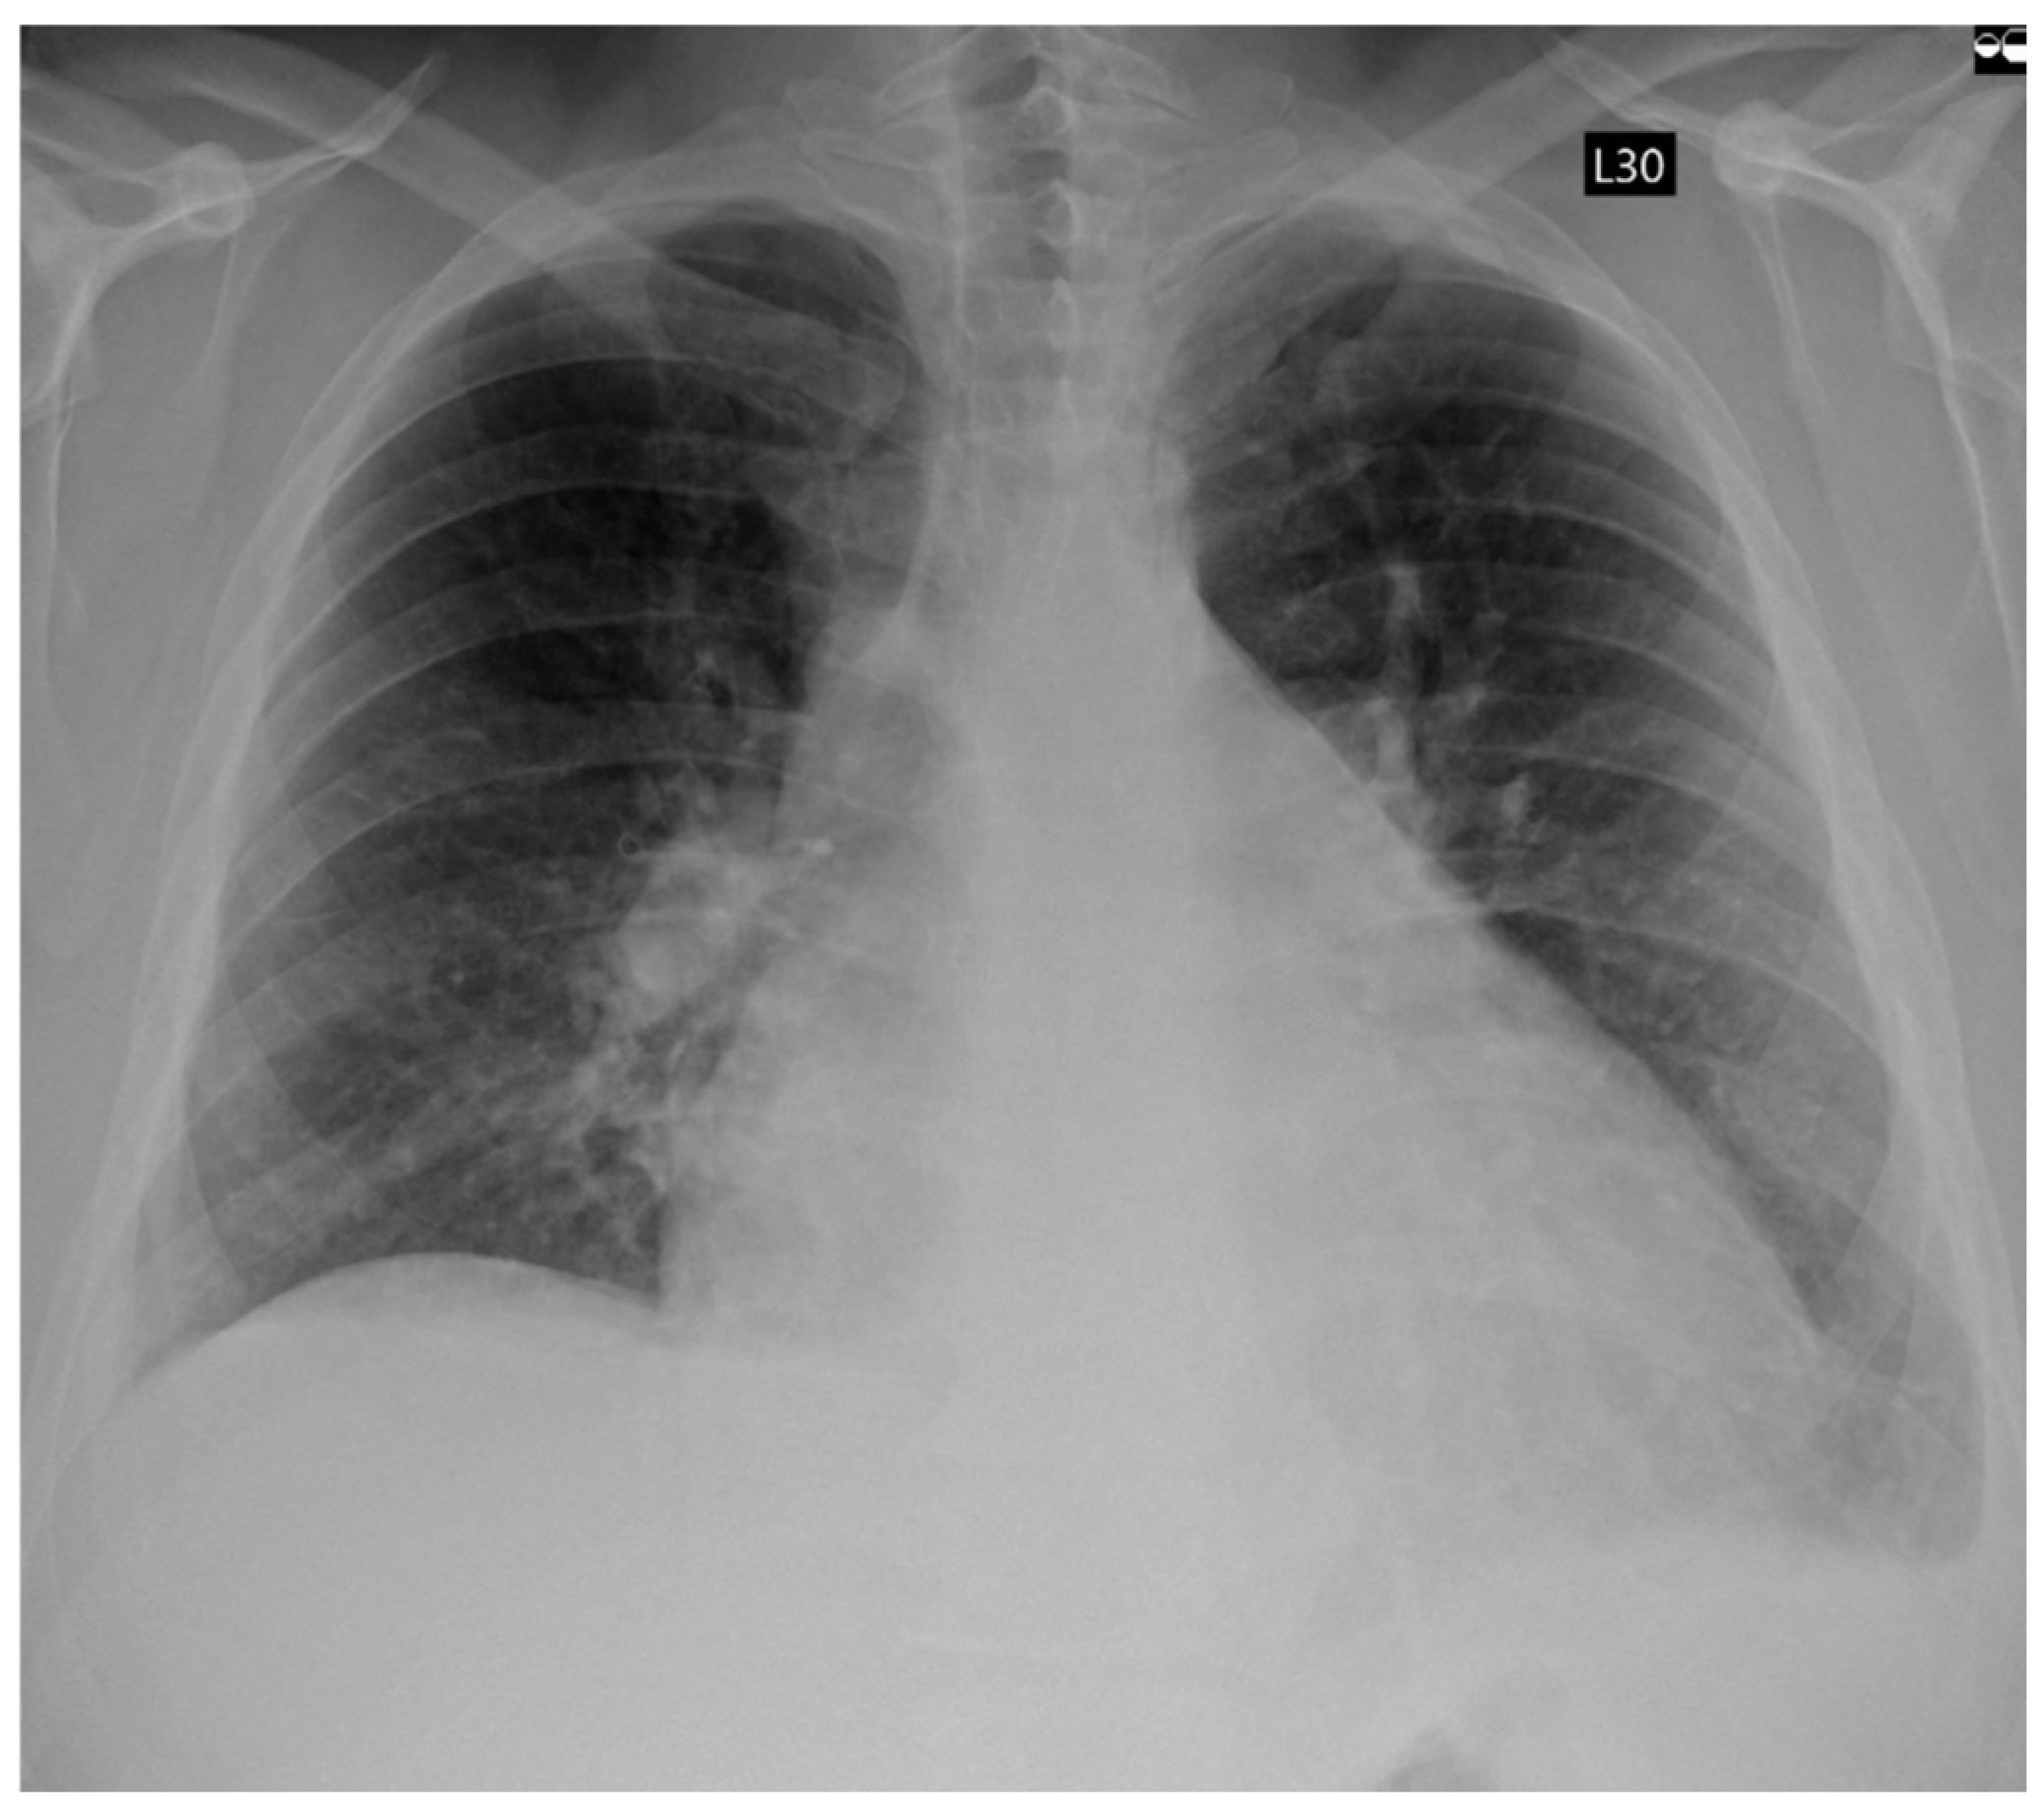

A 42-year-old male patient, previously healthy, physically active, and professionally employed, was referred to the Emergency Department due to progressive exercise intolerance persisting for several weeks. Several days prior, during a visit to a primary care physician, the patient was diagnosed for the first time with AF. Rate control therapy (bisoprolol 5 mg once a day) and oral anticoagulation (apixaban 5 mg twice a day) were initiated. However, despite the implemented treatment, the patient reported no symptomatic improvement. Electrocardiography revealed AF with a rapid ventricular response of approximately 160 beats per minute. Transthoracic echocardiography (TTE) demonstrated globally reduced left ventricular systolic function with a left ventricular ejection fraction (LVEF) of 25%, left ventricular dilatation (LVESD 55 mm, LVEDD 61 mm), left (LA 54 mm, LAA 36 cm2; LAVI 58.13 mL/m2) and right (RAA 22.1 cm2) atrial enlargement, and moderate functional mitral regurgitation. Physical examination revealed signs of congestion in both the systemic and pulmonary circulations. Laboratory investigations showed elevated levels of natriuretic peptides, as well as markers of hepatic and renal dysfunction. Chest radiography demonstrated features of pulmonary congestion and a small amount of pleural effusion in both pleural cavities (Figure 1).

Figure 1. Chest X-Ray showing fluid congestion in admission.